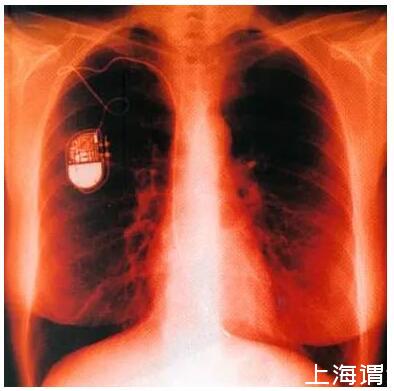

按應(yīng)用形式分類有:植入式傳感器、暫時植入體腔(或切口)式傳感器、體外傳感器、用于外部設(shè)備的傳感器

植入式傳感器